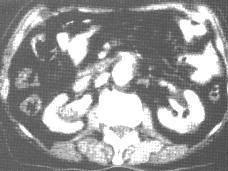

问题 女,42岁,活动后出现右腰部钝痛。尿常规:红细胞10~15/HP,白细胞5/HP:B超:右肾盂内2.0cm×1.5cm不均匀低回声,界不清。 为明确诊断还需要进行的检查是 ( )

选项 A、CT和尿培养 B、KUB及IVP C、肾动脉造影 D、磁共振检查 E、膀胱镜检查

答案 B